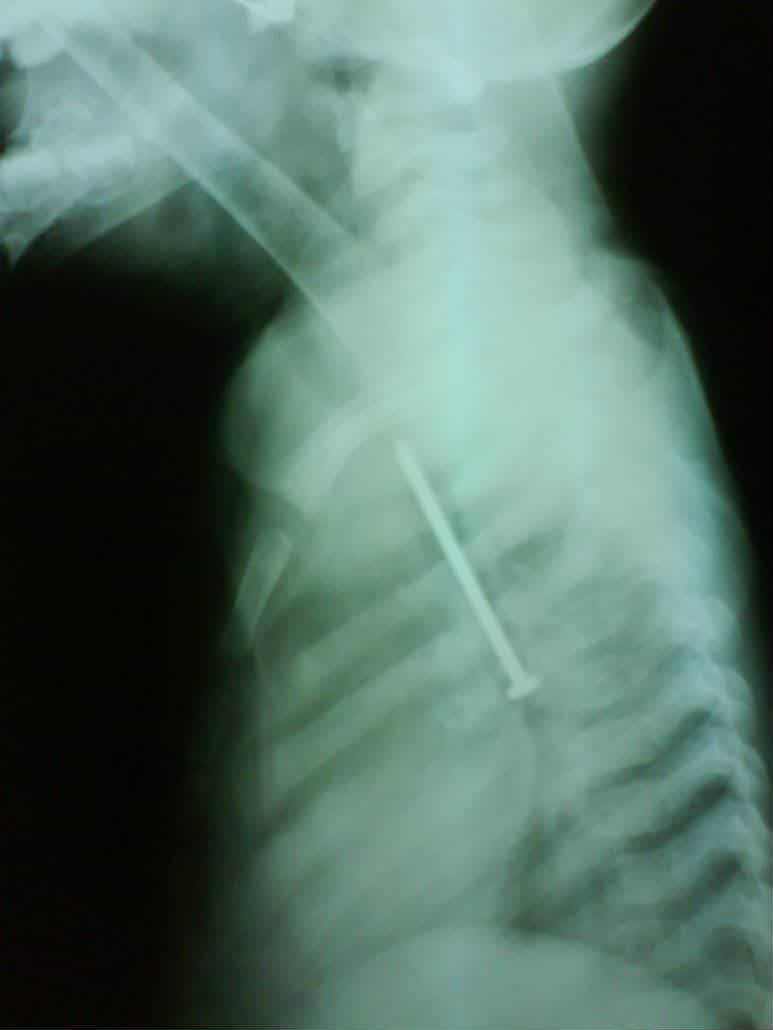

وأضاف قائلًا: "كانت الطفلة في حالة طبيعية تمامًا، تتنفس بشكل جيد ولا تعاني من أي صعوبة في البلع، لكن أمام إصرار الأم على أنها بحثت جيدًا في المنزل، قررت إجراء أشعة على صدر الطفلة، لتظهر المفاجأة الصادمة: مسمار طويل يمتد بطول القفص الصدري تقريبًا."

وأشار إلى أنه تم إدخال الطفلة إلى غرفة العمليات على الفور، وتمكن الفريق الطبي من استخراج المسمار بنجاح، دون حدوث أي إصابة أو مضاعفات.